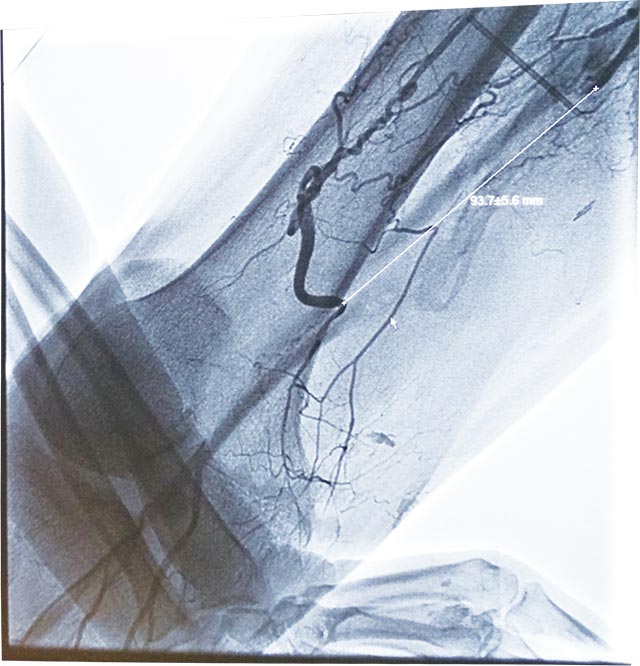

•   人工血管轉(zhuǎn)流術治療陳舊外傷性右股淺動脈閉鎖 日期:2017-02-23 08:39:00 點擊:2370 好評:36

家住濰坊市臨朐縣的王先生,17年前曾因右下肢外傷曾行二次手術,作股淺動脈自體大隱靜脈搭橋術,術后傷處瘢痕組織明顯。近1年來右足部出現(xiàn)疼痛不適,右踇趾甲床處出現(xiàn)頑固性感染并化膿。輾轉(zhuǎn)多家醫(yī)院就診都...